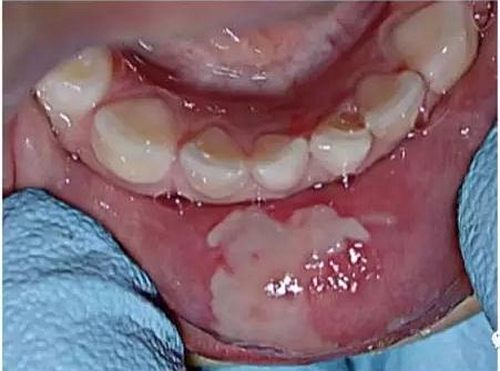

由于使用的麻醉劑,患兒將嘴唇咬傷